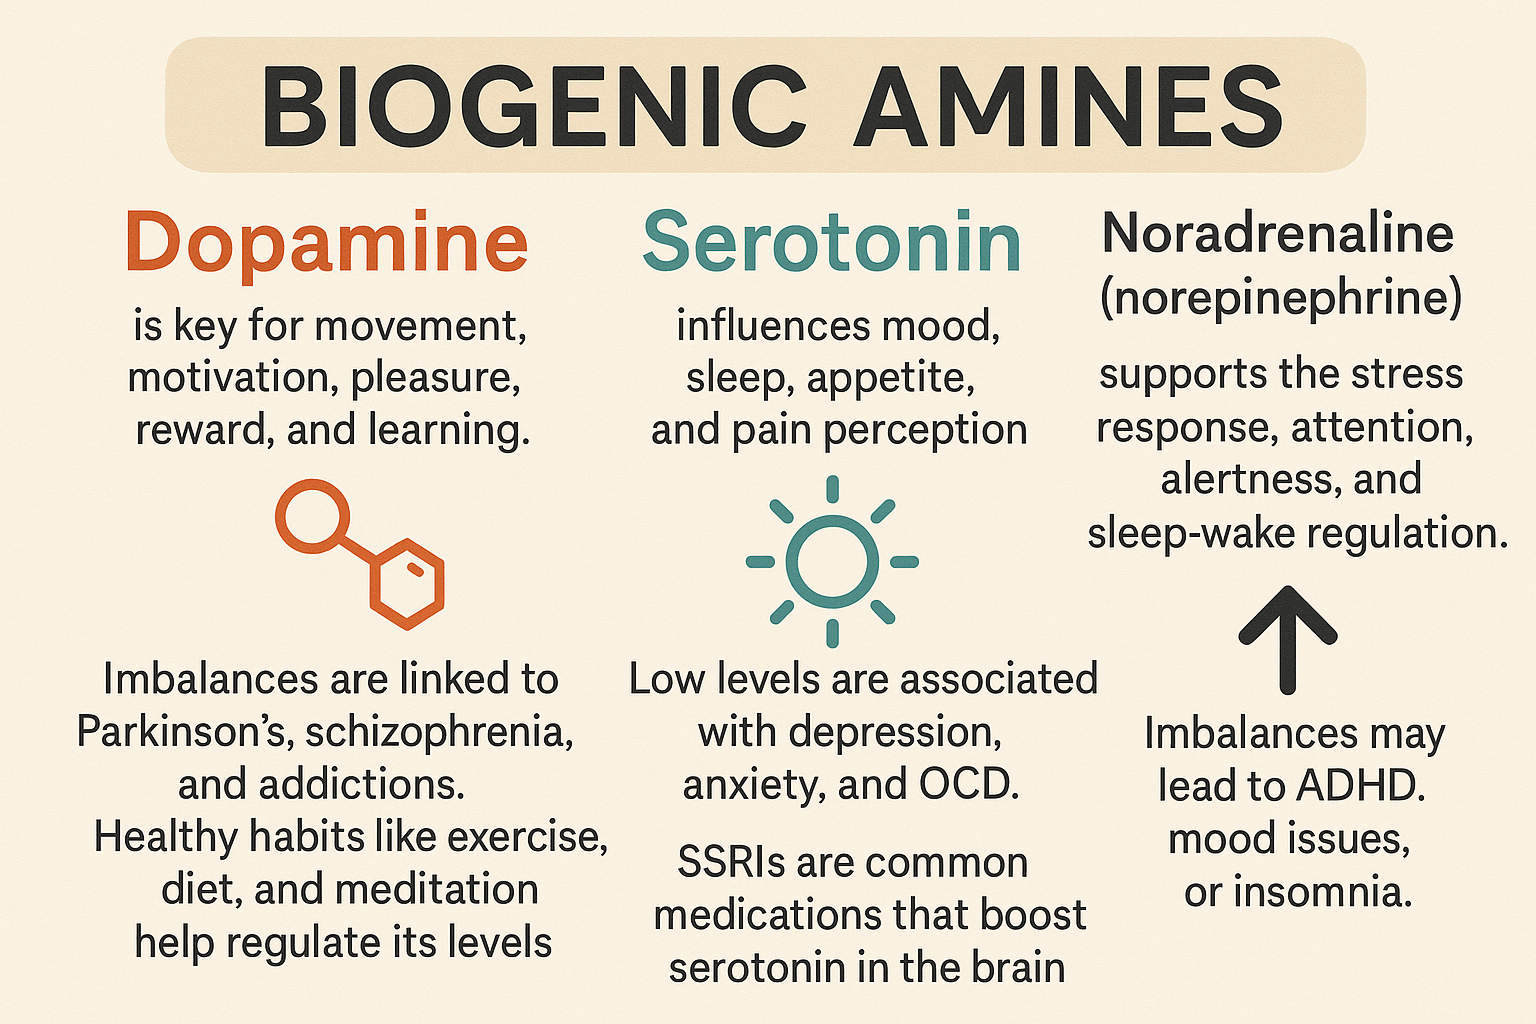

Neurotransmisores

Son sustancias químicas que permiten la comunicación entre las neuronas en el sistema nervioso y piezas fundamentales del engranaje cerebral. Sin ellos, no podríamos movernos, sentir, pensar ni aprender. Actúan como mensajeros que transmiten señales de una célula nerviosa a otra a través de la sinapsis y reforzada por la mielina. Esta función es fundamental para el funcionamiento del cerebro y, en general, del organismo, ya que regula desde procesos automáticos como la respiración o el ritmo cardíaco, hasta funciones complejas como el aprendizaje, la memoria, las emociones y la conducta.

Cuando una neurona se activa, libera neurotransmisores en la sinapsis. Estas moléculas se acoplan a receptores específicos en la neurona siguiente, generando un nuevo impulso eléctrico o modificando la actividad de esa célula. Posteriormente, los neurotransmisores pueden ser degradados, reciclados o reabsorbidos por la neurona original mediante un proceso llamado recaptación.

El equilibrio químico de los neurotransmisores es delicado. Su exceso o déficit puede causar trastornos como ansiedad, depresión, esquizofrenia, Alzheimer o Parkinson.